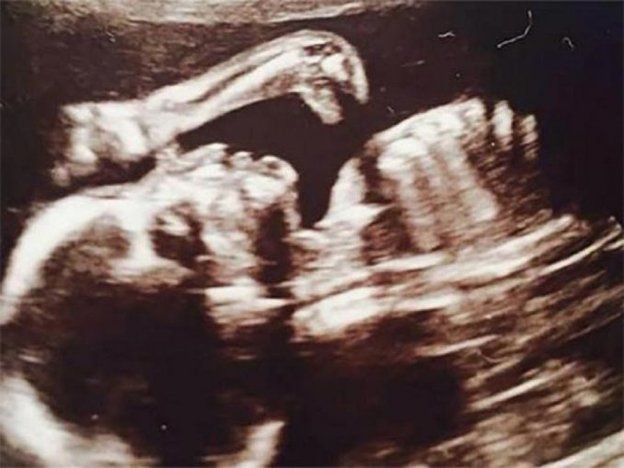

Inicio Mundo 26 de julio de 2015 - 07:59 Un dinosaurio apareció en una ecografía Por UNO La curiosa situación se desató luego de realizar los estudios correspondientes para la llegada de Ruthie, la beba que espera la británica Leanne Sullivan.La mujer, luego de ver las imágenes, se llevó una gran sorpresa. las más leídas Sobrenatural El sacerdote Marcelo De Benedictis detalló un exorcismo en el Lagomaggiore Por Redacción de UNO Telekino Telekino: resultados del sorteo 2423 del domingo 12 de abril Por Paula Alonso ¿Jugaste? Quini 6: los resultados del sorteo 3364 del domingo 12 de abril Por Fabricio Panella Causa compleja Cueveros, sicarios, un prestamista: el juicio por un asesinato en la Cuarta Sección Por Redacción de UNO Lo que se lee ahora Mundo Un joven salvó a su amigo de una descarga eléctrica en una cancha de fútbol 5 Te puede interesar Elecciones Fin de una era en Hungría: tras 16 años, cayó Viktor Orbán y el gobierno de Milei saludó al ganador Héroe Un joven salvó a su amigo de una descarga eléctrica en una cancha de fútbol 5 Segunda misión desde 2025 Una flota de 70 barcos partió desde España con ayuda humanitaria para la población de Gaza